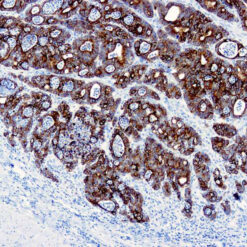

This antibody recognizes insoluble elastin, α-elastin, soluble non-cross linked precursor of elastin (tropoelastin). Elastin is an important polymeric protein of connective tissue that imparts elasticity to vertebrate elastic tissues.

| Cellular Localization | Connective tissue |

| Positive Control Tissue | Heart, Kidney |